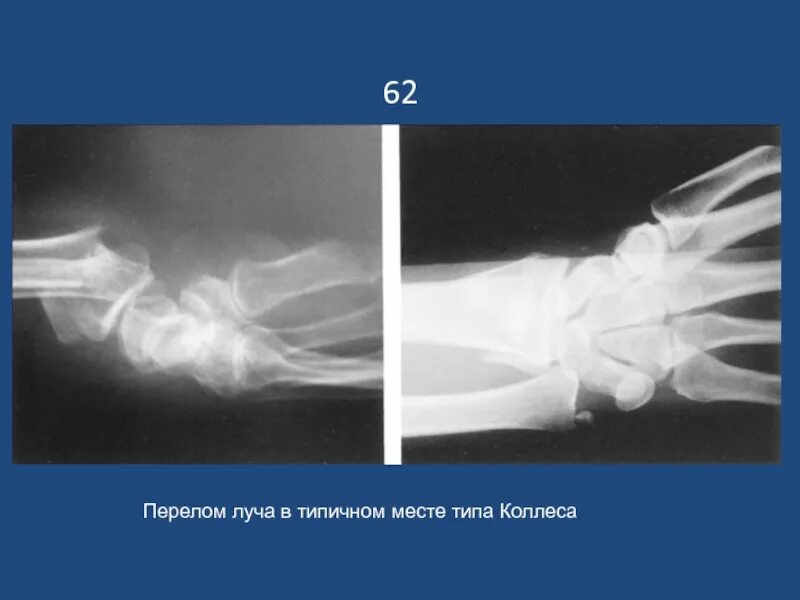

Перелом луча в типичном месте код мкб